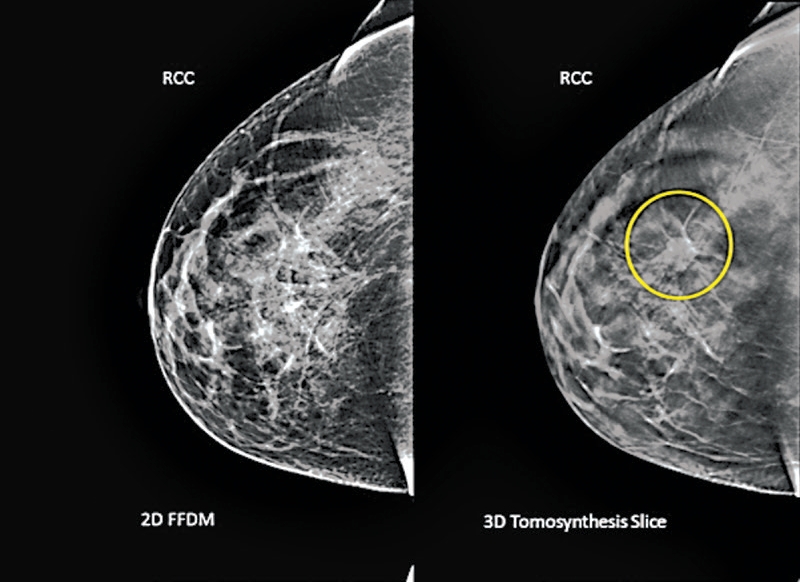

Este ano, milhões de mulheres passarão pelo novo exame, a tomossíntese. O procedimento é parecido com uma mamografia de rotina, sendo que na mamografia a máquina fica parada, enquanto na tomossíntese ela se move ao redor da mama. Às vezes chamada de mamografia em 3-D, o exame tira muitos raios X em ângulos diferentes para criar uma imagem tridimensional da mama. O exame foi homologado nos Estados Unidos em 2011.

O estudo analisou os registros de 13 centros de mamografia nos EUA antes e depois de acrescentarem a tomossíntese. Os pesquisadores compararam a taxa de detecção de câncer, quantas vezes as mulheres precisaram remarcar mais exames para verificação das novas descobertas, e qual a proporção dos retornos e das biópsias que de fato descobriram o câncer.